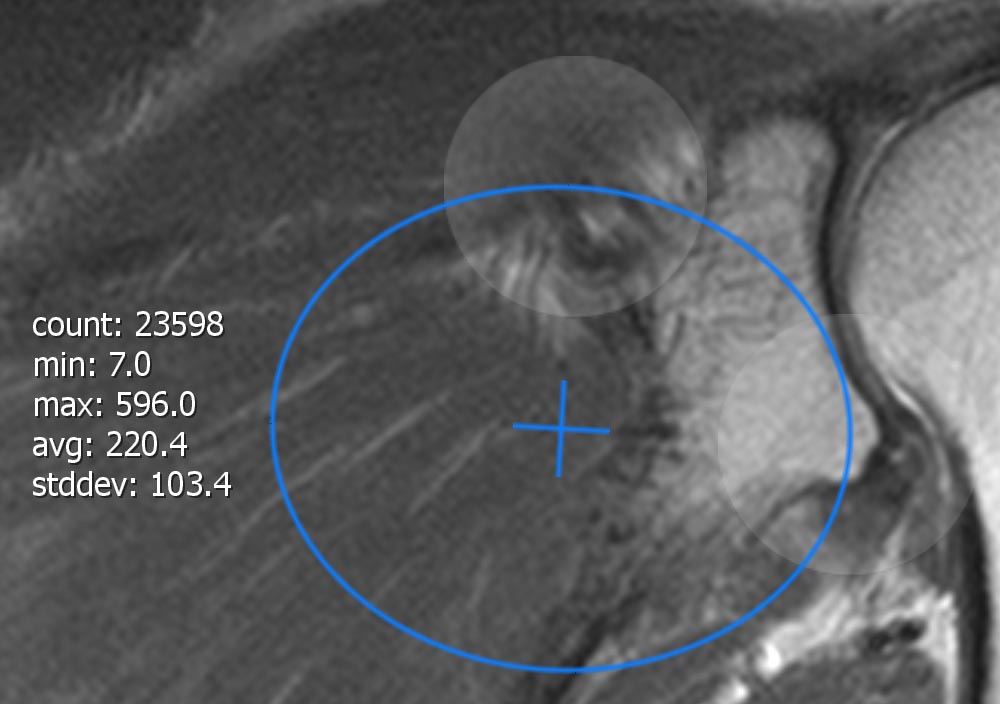

11.1.7. Region of interest

Über das "Region of Interest"-Werkzeug können Sie eine "Region of Interest" (ROI) in ein Schichtbild einfügen. Nach dem Einfügen ist das ROI standarmäßig aktiv und daher können Sie sofort mit ihr interagieren. Der aktive Status wird durch eine orangene Färbung der Ellipse angezeigt. Bei inaktivem Status ist die Ellipse hingegen weiß eingefärbt. Durch Tappen, Halten und Bewegen des Ellipsenzentrums (sichtbar durch eine Kreuzung) kann die ROI verschoben werden. Mithilfe der zwei weiß-transparenten Kreise, auch Touch-Handles genannt, welche sich an der Konturlinie der Ellipse befinden, kann per Touch-Interaktion die Ellipse sowohl vergrößert als auch rotiert werden. Gegenüber der Touch-Handles befindet sich ein zusätzlicher Informationstext, welcher folgende berechneten Werte über die in der ROI liegenden Pixel enthält:

-

area: Fläche (optional, wenn Bild Spacing korrekt).

-

count: Anzahl der Pixel innerhalb der ROI.

-

min: Kleinster in der ROI enthaltene Grauwert.

-

max: Größter in der ROI enthaltene Grauwert.

-

avg: Durchschnittlicher Grauwert über alle in der ROI enthaltenen Grauwerte.

-

stddev: Standardabweichung / gemittelter Abstand der Streuung aller Grauwerte zum durchschnittlichen Grauwert der in der ROI enthaltenen Pixel.